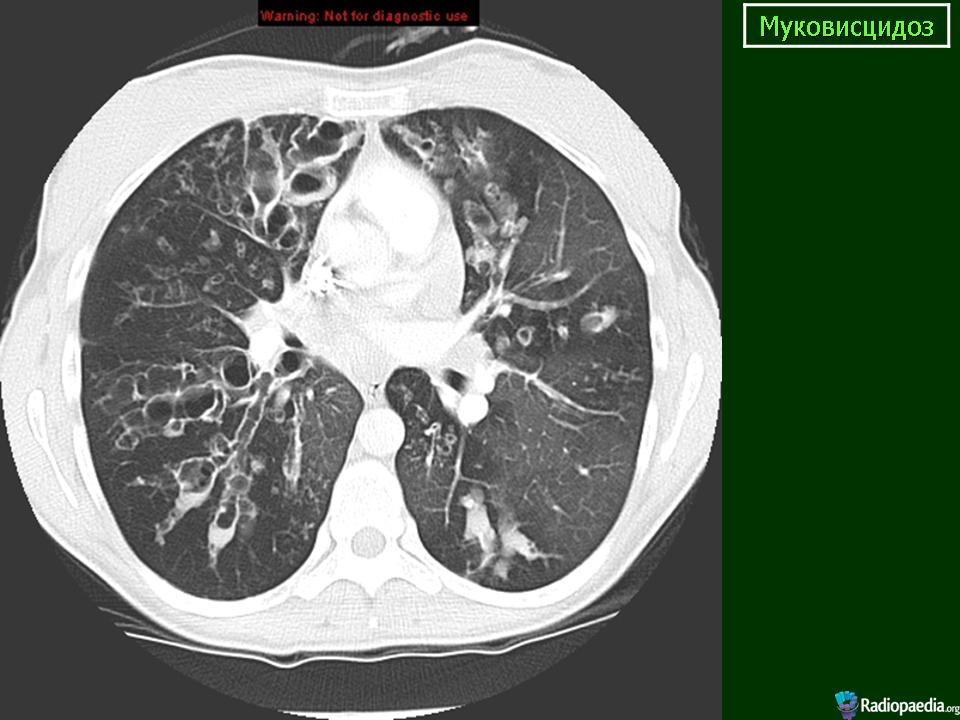

Муковисцидоз. Саркома мягких тканей. Метастатическое поражение легких.

На обзорной рентгенограмме органов грудной клетки в прямой и правой боковой проекции: легочный рисунок с обеих сторон усилен деформирован. Во всех отделах видны множественные разнокалиберные просветления, кольцевидные образования, очаги, фокусы уплотнения неоднородной структуры округлой, овальной или неправильной формы размерами от 0,5 см - 2,0 см диаметром до 4,0х1,5см. Корни легких уплотнены, от них отходят грубые тяжи.

Компьютерные томограммы. В легких с обеих сторон просветы бронхов расширены, деформированы, стенки их утолщены. Видны множественные цилиндрические, мешотчатые и веретенообразные бронхоэктазы, отдельные из которых заполнены секретом. Отмечается неравномерное утолщение междольковых перегородок, перибронхиального и периваскулярного интерстиция. В S10 нижней доли правого легкого, а так же в S9 и S10 нижней доли левого легкого выявляются метастазы в виде мягкотканой плотности округлой формы образований с четкими контурами.